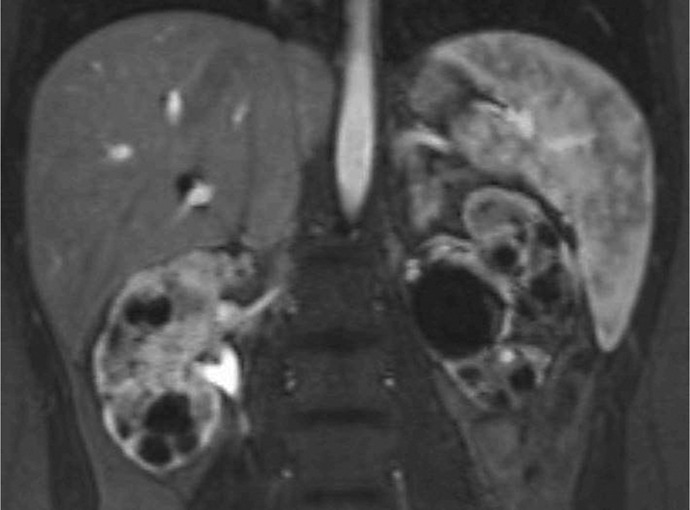

Case presentation: We report an 18-year-old female with congenital ciliopathy presenting with declining renal function and an increase of serum creatinine to 1.7 mg/dL. A 24-h urine collection yielded 0.8 g of creatinine and 500 mg of total protein. Imaging was conducted and genetic studies were repeated as her early childhood results were not available. MRI revealed numerous bilateral renal cysts consistent with progression of ciliopathy-associated PKD. Genetic testing confirmed the presence of a novel c.1332del frameshift mutation in the OFD1 gene, prematurely truncating the OFD1 protein. Modifications to diet and hydration to preserve renal function and delay progression to ESRD were initiated.